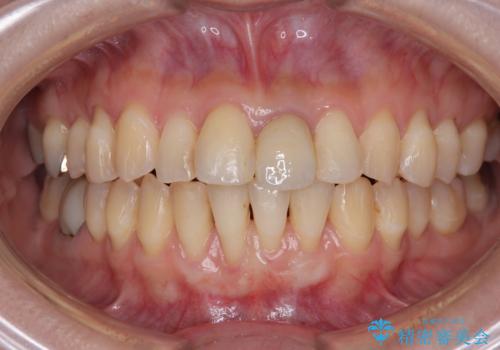

- 他院で矯正治療を終えた結果、下顎前歯の歯肉が退縮してしまい、歯根が見えていることが気になるとのことで来院された患者様です。

歯肉退縮に対して、上顎からの結合組織移植術(CTG)により、歯根の被覆を行うとともに、歯肉の厚みを増すことで将来の退縮リスクを抑制することとしました。

一度の処置で大幅に露出部の被覆に成功しましたが、更なる厚みと被覆を希望されて2回目の処置を行いました。

歯根部周辺の歯肉が非常に分厚くなり、今後の退縮リスクが大きく軽減されました。